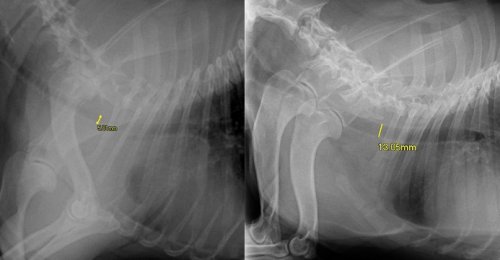

Een te smalle luchtpijp kan alleen goed met een röntgenfoto beoordeeld worden.